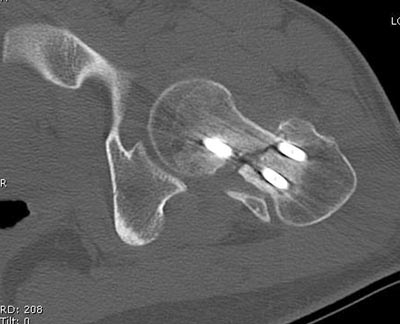

несращения! По истечению 4 месяцев появились признаки варусной

деформации. На СТ срезах несращение шейки и бедра. Риминг, замена на

более толстый гвоздь и вальгусная остеотомия.